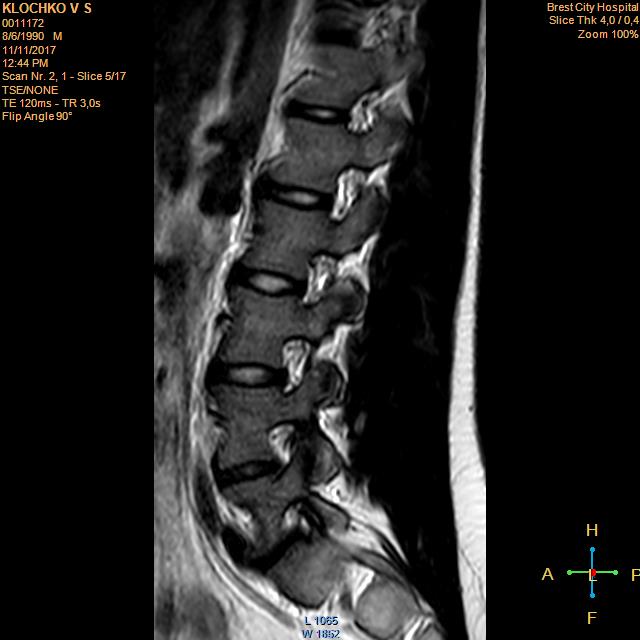

Тренировки с межпозвоночной грыжей.